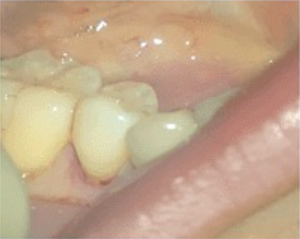

術後6ヵ月で治癒しました。